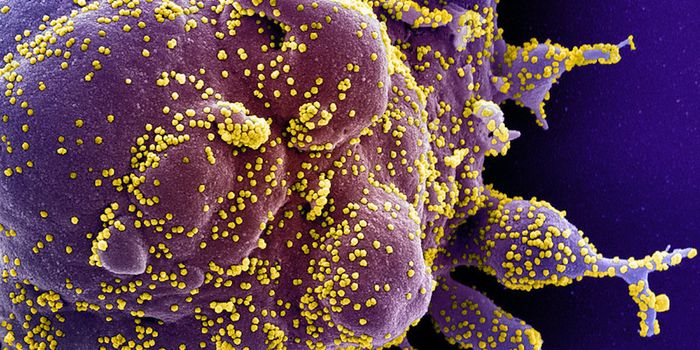

APR 04, 2022Cell & Molecular BiologyAbout 1.5 million new HIV infections are thought to have occurred last year, and while COVID-19 has dominated concerns a ...